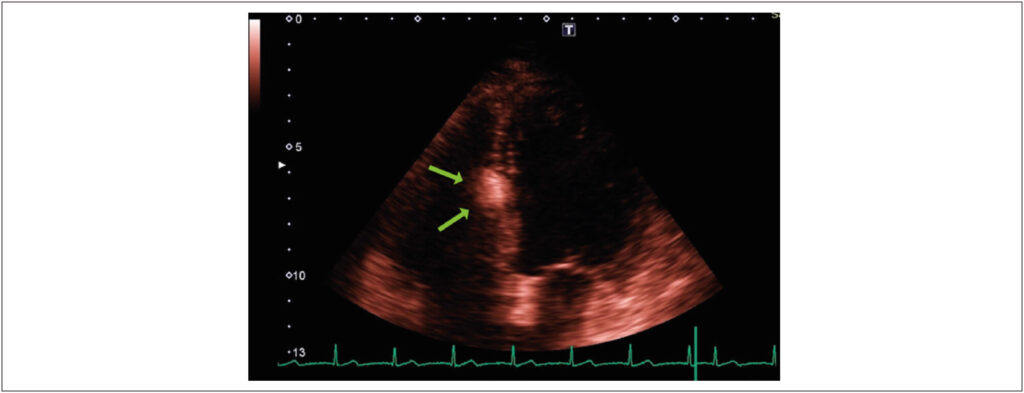

Primary cardiac tumors are a rare but mostly benign pathology found in up to 0.03% of autopsies. Among these benign tumors, with an incidence of 8.5%, lipomas are often located in the interatrial septum. When located in the interventricular septum, they are considered an even more unusual pathology with an unknown real prevalence. In most cases, the diagnosis is made incidentally on cardiovascular imaging and confirmed by histopathological examination. They are more commonly asymptomatic or feature nonspecific symptoms, but these lipomas can progress with arrhythmias, valve dysfunction, heart failure, and death, which highlights the importance of cardiovascular imaging methods in the differential diagnosis and to guide appropriate therapy. This report describes the case of a patient with an incidental echocardiographic finding of a cardiac mass located in the interventricular septum, followed by cardiac magnetic resonance imaging to better characterize the lesion and demonstrate its characteristics compatible with lipoma.